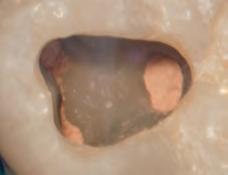

Sable Seek caries indicator contains FD&C dyes, and Seek caries indicator contains D&C dyes in a glycol base. Both are used to stain carious and demineralized dentin.

Seek and Sable Seek caries indicators stain carious and demineralized dentin and can be very useful for difficult-to-see areas, for example; undercuts of preparations, dark dentin, areas along the DE junction, etc. Green Sable Seek caries indicator helps visualization of decay in deep caries cases to help avoid pulp exposures.